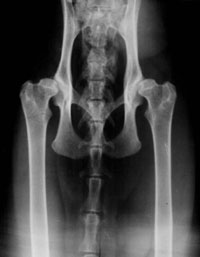

Dysplasie de la hanche (HD)

Radiographie d’une chat avec des hanches normales

- Quand on entend parler de dysplasie des hanches et de radiographies, la plupart du temps il s’agit de chiens. Mais ce problème existe aussi couramment chez le chat. La dysplasie des hanches est une malformation héréditaire de l’articulation de la hanche (du pelvis) lorsqu’elle n’est pas assez profonde. A cause de cela, l’os ne se place pas comme il faut dans l’articulation, et un frottement des deux s’ensuit, ainsi qu’une dégénérescence du cartilage. Peu à peu le cartilage disparaît, laissant une surface articulaire d’os à os qui provoque des douleurs. Le corps ne peut produire du cartilage, et tente de se défendre en produisant encore plus de matière osseuse, ce qui ne fait qu’aggraver le problème.

- Les chats en général ne montrent pas leur souffrance, et peuvent souffrir de dysplasie des hanches sans boiter du tout. En revanche, ils bougent alors avec plus de précautions, ou bougent moins qu’un chat indemne; ils peuvent aussi éviter de sauter. Des chats avec une dysplasie légère peuvent ne pas souffrir du tout.

- Depuis janvier 2000, le Swedish Maine Coon Club garde un registre de radios des hanches. On recommande de tester tout chat reproducteur avant de l’utiliser dans un programme d’élevage afin de minimiser les problèmes de dysplasie dans la race. Ce registre est officiel et son but est de définir la fréquence de la dyplasie de la hanche chez le Maine Coon. Le Swedish Maine Coon Club travaille en collaboration avec le docteur en médecine vétérinaire Lars Audell qui est le spécialiste en ce domaine en Suède. Il envoie les radios évaluées et les résultats des tests au Swedish Maine Coon Club, où ils sont enregistrés et rendus publics 60 jours après que le propriétaire a pris connaissance des résultats. La copie originale des radios et des résultats est renvoyée au propriétaire du chat dès que le Club a reçu le paiement.